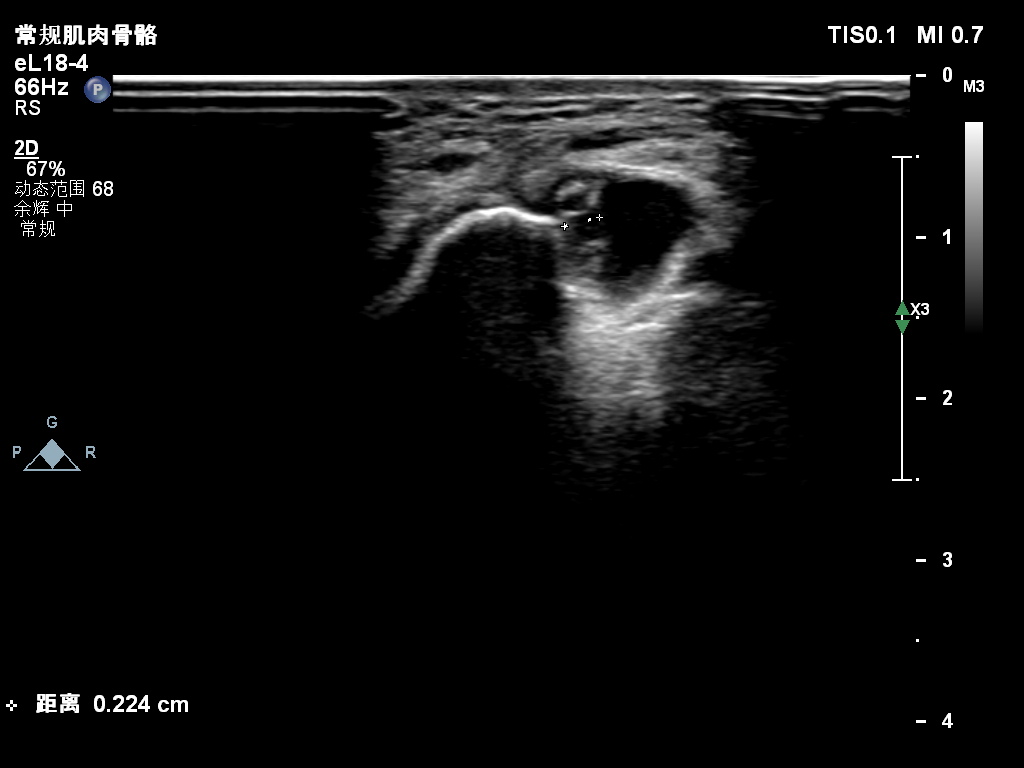

超声所见:右侧尺神经于肘管上段增粗,较粗处横截面积约0.25cm²,神经外膜及神经束膜显示欠清晰,神经纤维连续性可。尺神经走行至肘管处受压变扁,局部尺神经外膜处可见囊性结构并向肘管远段延伸,边界清,形态不规则,内可见多条带状分隔。CDFI:囊性结构内未见明显血流信号。

肘管处尺神经受压变扁